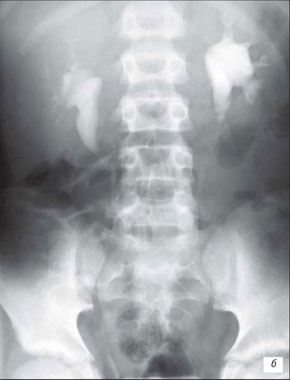

Рис. 16. Экскреторная урограмма (15-я минута).

Гипоплазия правой почки - она небольших размеров, чашечки сближены, шейки их укорочены, форниксы деформированы.